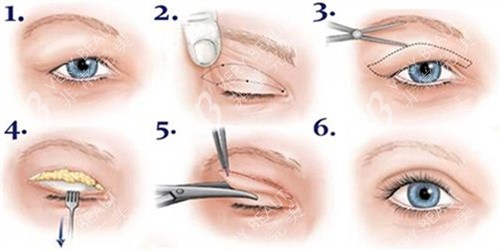

手术方式多样

他熟悉全切、埋线等各类手术操作方式。对于眼皮薄、皮肤紧致的年轻人,他会推荐埋线双眼皮,这种方式改善快,几乎无疤痕,若不喜欢还可随时拆掉;而对于眼皮松弛、肿眼泡等情况,他会采用全切双眼皮,能有效去除多余的皮肤和脂肪,结果持久。

在手术过程中,王博谦医生手法轻柔、操作精细,能较大程度减少对眼部组织的损伤,降低术后肿胀和疼痛的程度,缩短修复时间。他还擅长运用小创口技术,使双眼皮线条流畅自然,宛如天生。